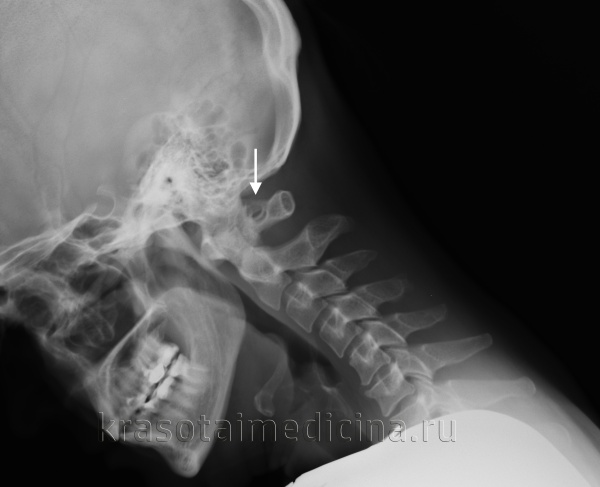

При обращении пациента с симптомами недостаточности кровообращения в вертебро-базилярном бассейне головного мозга в первую очередь производят рентгенографию черепа и рентгенографию позвоночника в шейном отделе. Аномалия Кимерли, как правило, достаточно четко визуализируется на боковых рентгенограммах области краниовертебрального перехода. При наличие ушного шума для исключения лор-патологии (кохлеарный неврит, хронический средний отит, лабиринтит) может потребоваться консультация отоларинголога, проведение аудиометрии и других исследований слуха. Производится также исследование вестибулярного анализатора (вестибулометрии, электронистагмографии, стабилографии).

Рентгенография ШОП (боковая проекция). Дополнительное костное кольцо в области задней дужки С1 (аномалия Кимерли)